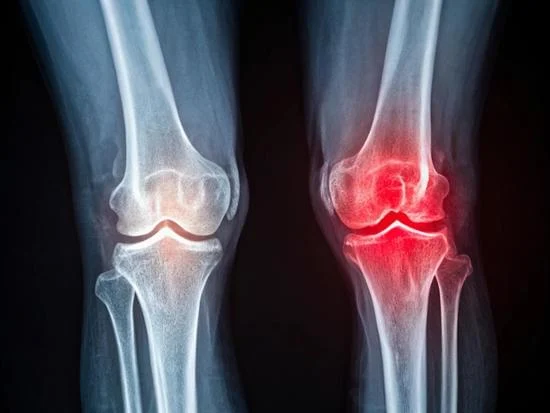

Knee Replacement

Knee Replacement Surgery